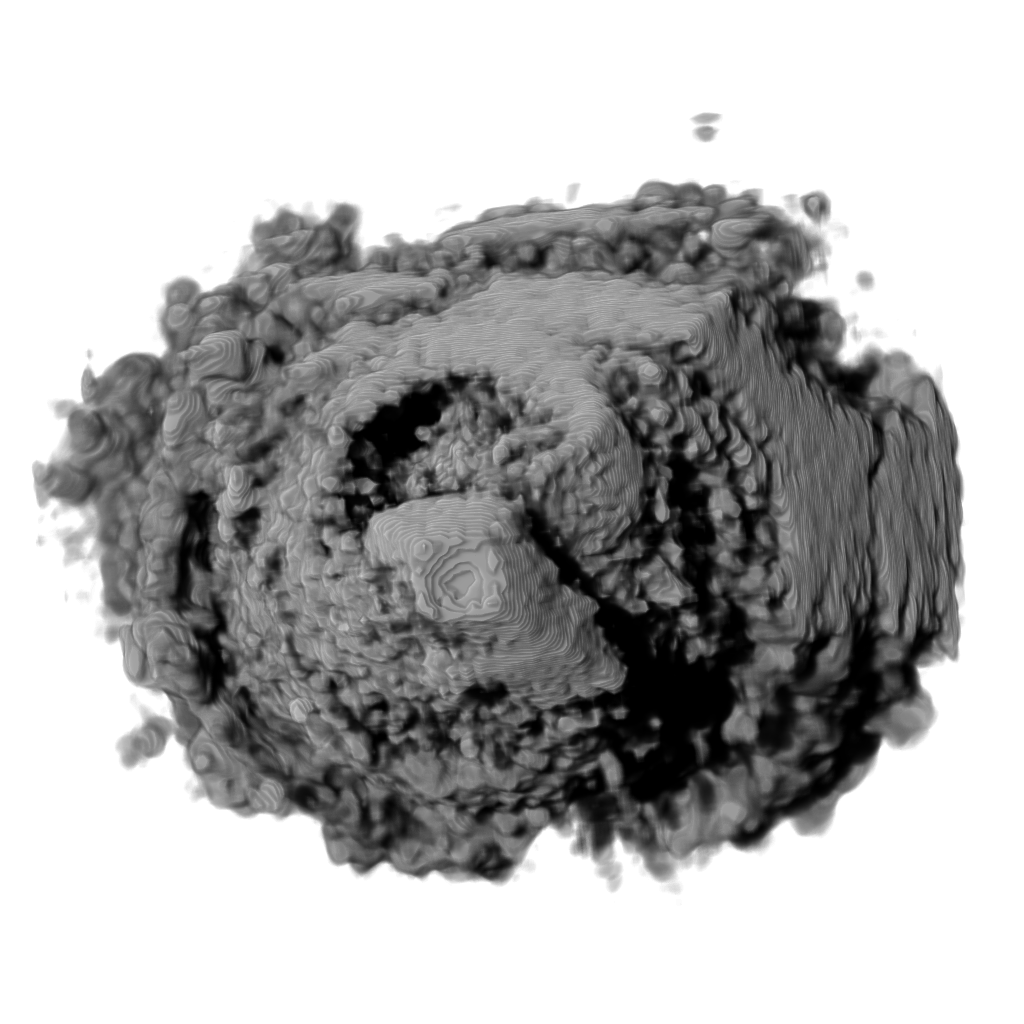

Recent works show that global illumination models based on gradient-free methods are suitable for rendering ultrasound volumes Ropinski10 ; solteszova10 . Ropinski et al. described a volumetric lighting model which simulates scattering and shadowing Ropinski10 . They use slice-based volume rendering from the view of the light source to calculate a light volume and raycasting to render the final image (see Figure 7b). A perceptual evaluation of the generated images indicates, that the proposed model yields stronger depth cues than gradient-based shading. Šoltészová et al. presented a single-pass method for simulation of light scattering in volumes solteszova10 . Light transport is approximated using a tilted cone-shaped function which leaves elliptic footprints in the opacity buffer during slice-based volume rendering. They use a slice-based renderer with an additional opacity buffer. This buffer is incrementally blurred with an elliptical kernel, and the algorithm generates a high-quality soft-shadowing effect (see Figure 7c). The light position and direction can be interactively modified. While these two techniques have been explicitly applied to 3D US data, the application of other volumetric illumination models potentially also improves the visual interpretation of 3D US data. Figure 8 shows a comparison of six different shading techniques as applied to a 3D US scan of a human heart. While the first row of Figure 8 shows examples for the already addressed shading techniques, the second row shows three alternative approaches. Figure 8d incorporates scattering of light in volume data, as proposed by Kniss et al. kniss02halfangle . Their slicing technique allows textured slices to be rendered from both light and viewing direction simultaneously. By sampling the incident light from multiple directions while updating the light’s attenuation map, they account for scattering effects in slice-based volume rendering. Figure 8e shows the application of the directional occlusion shading technique schott09directionalocclusion . This technique constrain the light source position to coincide with the view point. Finally, Figure 8f shows the application of a technique based on spherical harmonic lighting lindemann10materials .

Refer to caption

(a)

(b)

(c)

Figure 7: (a): Diastole of the aortic valve on a modern ultrasound workstation using color-coding based on depth. (b): Rendering of 3D ultrasound of human heart with shadowing from the work of Ropinski et al. Ropinski10 and (c) rendered using the technique presented in the work of Šoltészová et al. solteszova10 .

Figure 8: Comparison of six volume shading models as applied to a 3D US scan of a human heart.

Advanced illumination techniques are being now implemented in the commercial ultrasound workstations. Some workstations use additional color coding based on depth. Deeper tissues are colored with cold tones such as blue while close regions have red and orange tones. This effect has been firstly described by Einthoven Einthoven1885 and is also referred to as chromostereopsis Allen81 . Figure 7a shows a chromatic depth-encoding rendering of a 3D human heart in a modern ultrasound workstation.